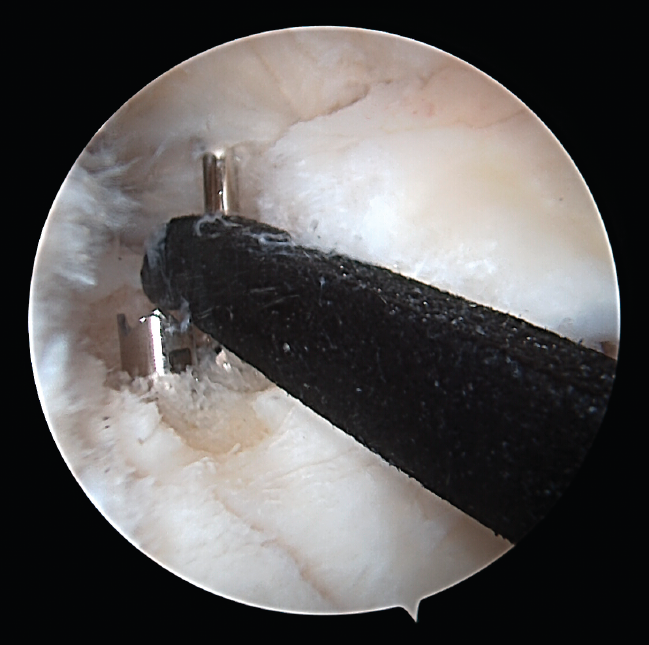

Figure 7. Final repair (right knee).

One of the patients in the standard guide group required modification of the perforation secondary to intraarticular exit of the Kirschner wire in a position different from that planned, due to positioning difficulties caused by the existence of a narrow intercondylar groove and prominent spines. The 3D printed guides adapted on both supports to the bone surface of the tibia and were precise in conducting the guide needles towards the planned position (Figures 6 and 7). There were no problems derived from friction between the metal of the needles and the bore of the customized guide, and handling was ergonomically satisfactory for the surgeon.